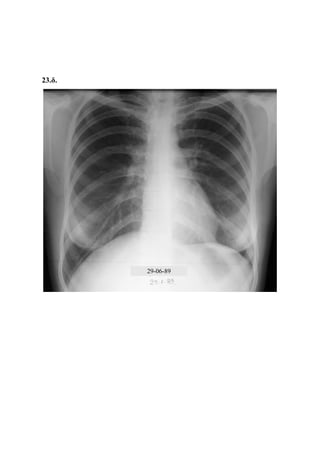

9. Μαθητής ηλικίας 12 ετών, υποβλήθηκε, σε πανεπιστημιακή παιδιατρική κλινική, σε αντιφυματική θεραπεία.

Από την επασβεστίωση του πυλαία αδένα σύστοιχα αποκλείστηκε η φυματιώδης φύση της βλάβης, και από το

γεγονός της παραμονής της σκιάς μετά την εφαρμογή της αντιφυματικής θεραπείας, επιβεβαιώθηκε. Η φύσις της

σκιάς παρέμεινε αμετάβλητη και παθογενετικά απροσδιόριστη. Επισήμανση: η ανεύρεση εν ενεργεία π.ε.

αναφέρεται σε πολύ μικρό ποσοστό, της τάξης του 1%, όπως προκύπτει από έρευνά μας σε 1644 περιπτώσεις

φυματικής πρωτομόλυνσης στο νομό Ροδόπης.

9.α.

9.β.

9.γ.

9.δ.

27-04-89